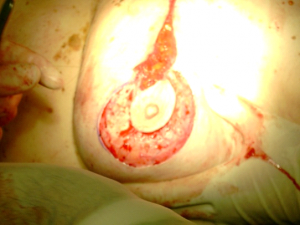

רוב המטפלים בסרטן השד על-ידי למפקטומיה משלבים טיפול קרינתי במנות של 6500R-5000R ויותר, כאשר חלק מהם (2000R) ניתן במרוכז על איזור (בוסט). עבודות שלא כללו קרינה כלל, הראו תוצאות פחות טובות מאשר הניתוחים הרדיקאליים, ולכן נראה שתנאי להצלחת הניתוחים המשמרים, הוא הוספת טיפול קרינתי לפרוטוקול. עבודות חדשות הראו שהקטנת מנת הקרינה ומשכה לא השפיעו לרעה על התוצאות לטווח ארוך ולכן בחולות שניתן להגדיל את המנה ולהקטין את מספר ההקרנות יקבלו אותו מינון מחולק ל-16 פעמים. גישה חדשנית לטיפול הקרינתי היא קרינה תוך ניתוחית. הרעיון מבוסס על כך שרוב החזרות המקומיות היו בסביבת הלמפקטומיה, ולכן יש להקרין את אותו איזור ולא את כל השד. בשיטה זו לאחר סיום הלמפקטומיה ולפני סגירת העור החולה מקבלת מנת קרינה בחדר ניתוח למיטת הלמפקטומיה, תהליך שנמשך כ- 45 דקות, ובסיומו העור נסגר מעל החלל. דווחים ראשוניים מראים שאין הבדל משמעותי בין החזרות המקומיות בחולות שקבלו קרינה על כל השד לבין אלה שקבלו קרינה רק למקום הלמפקטומיה.

כדי למנוע נזקי קרינה מידיים כמו כוויות על העור ונזקים מאוחרים כמו פגיעה בריאות ובלב יש לתכן את הקרינה בצורה כזו שהאיברים החיוניים יוצאו עד כמה שאפשר משדה הקרינה וכניסת הקרינה דרך העור תהיה כל פעם דרך מקום אחר (תמונה 41.12 ו-38.12).

שיטה אחרת למתן קרינה מקומית היא על ידי בריכתרפיה שבה מוחדרות מחטים מיוחדות המכילות חומר רדיואקטיבי – מחטי אירידיום - לאיזור הלמפקטומיה ומושארות שם עד קבלת מנת הקרינה הרצויה (איור 42.12).

גישה אחרת להקרין את השד היא דרך הכנסת צינורית שבקצה בלון הניתן לניפוח לחלל הלמפקטומיה ותפירת העור מעליו. כעבור 7-10 ימים מחברים את הצינורית לגנרטור שמפעיל אלמנט בבלון וכתוצאה מכך מופקים גלי קרינה לחלל הלמפקטומיה והרקמה סביבו. התהליך מבוצע מספר פעמים ביום במשך שבוע ימים ואז הבלון מרוקן ונשלף מהחלל הלמפקטומיה.